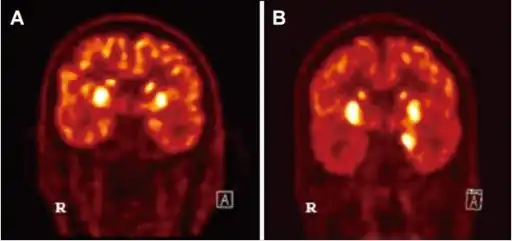

| Diagnosis of Autoimmune Encephalitis- a) basal ganglia hypermetabolism b) medial temporal hypermetabolsim | |